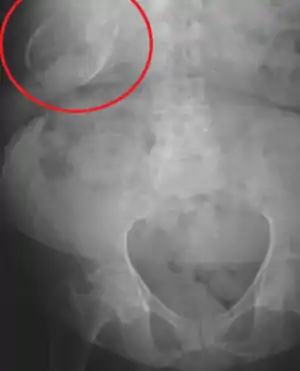

| Porcelain gallbladder on X-ray | |

Abdominal radiography (X-ray), abdominal ultrasound or CT scan.